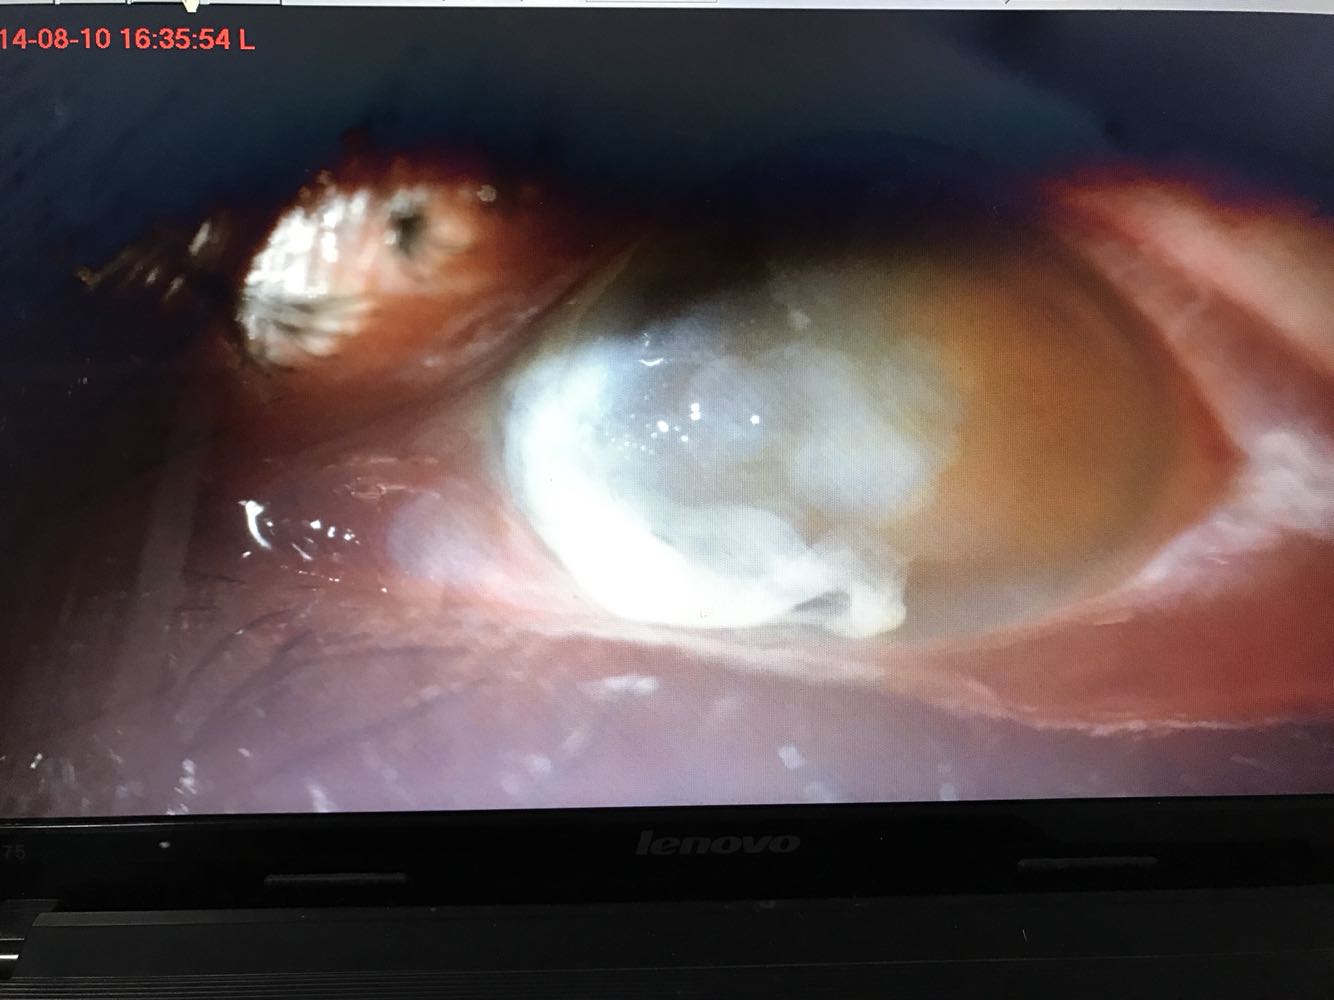

视力:右 1.0,左 眼前手动。左眼睑水肿痉挛,球结膜混合性充血+++,见大量脓性分泌物 。鼻侧角膜上皮部分脱落,基质弥漫性水肿。瞳孔大小可,对光反射迟钝,余窥不清。

这是治疗后的照片,视力0.1。